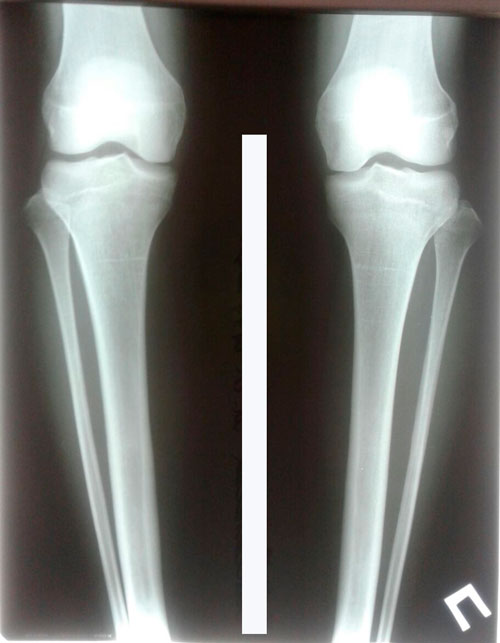

Дата операции 17.01.2018г.

Дата снятия аппаратов 21.05.2018г.

Срок лечения 123 дня.